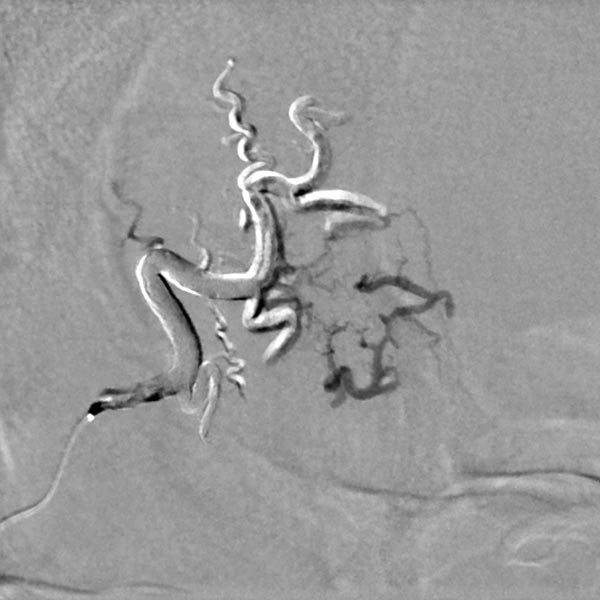

The conventional radiograph (same section as previous image) after completion of the embolization shows the complete cast specimen of the entire nidus with the radiopaque embolization material (cast). This accurately traces the anatomy and angiomorphology of the complete AVM, which is thus occluded.

Completion angiography with contrast injection into the right external carotid artery demonstrates complete occlusion of the nidus of the arteriovenous malformation. On account of the subtraction imaging technique, the cast appears white here (subtracted).

Comparison of the initial angiography images and the image of the cast specimen of the AVM completely filled with embolic agent demonstrate the completeness of the occlusion.